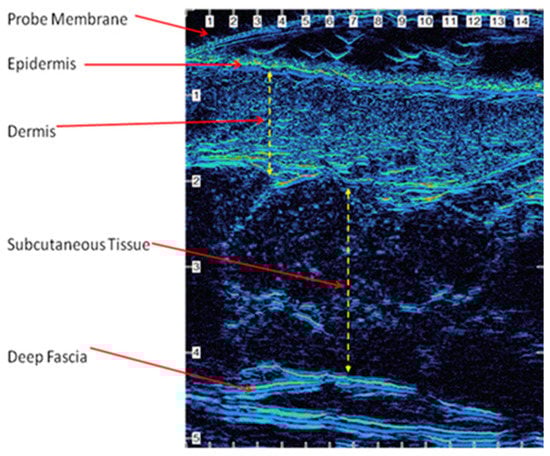

By analyzing the skin ultrasound images, we can obtain the thickness information of the different skin layers. Figure 4 shows the skin layers at different cross-sections in the high-resolution ultrasound image [6].

Figure 4. The skin layers at different cross-sections in a high-resolution ultrasound image [13].